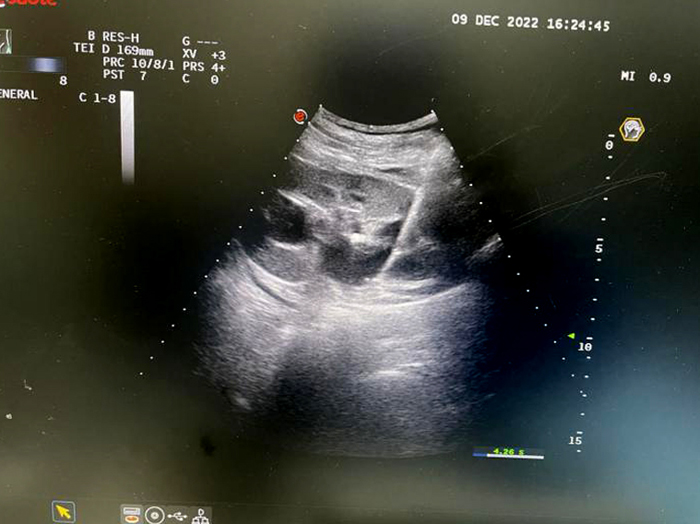

肝臟腫物微波消融術(shù)

子宮多發(fā)肌瘤微波消融術(shù)